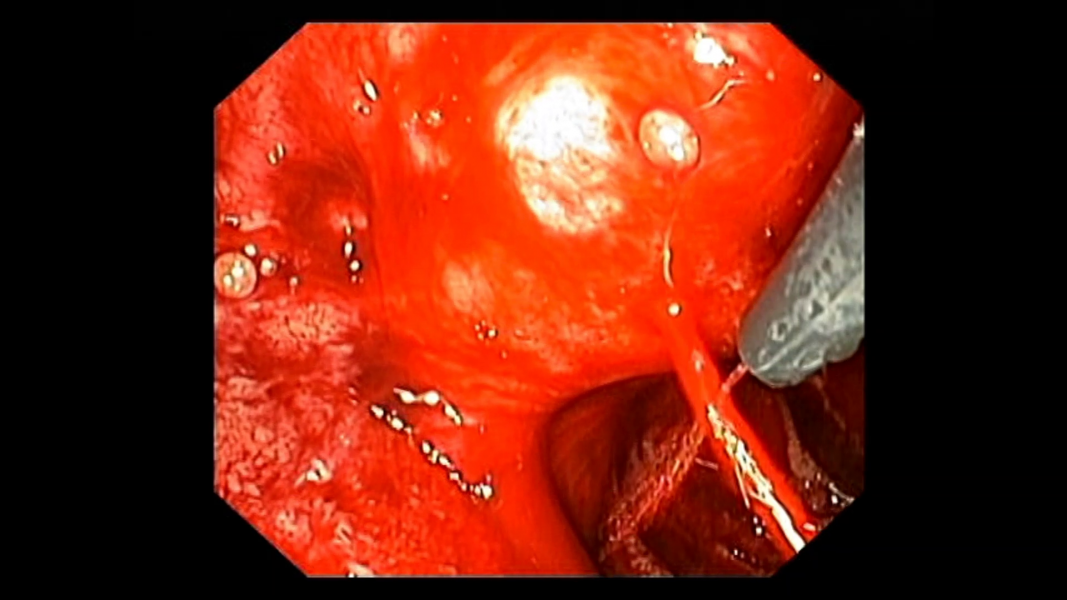

Massive Hemorrhage after Endoscopic Ultrasound Guided Fine Needle Aspiration of a Cephalopancreatic Cystic Lesion

Vídeos